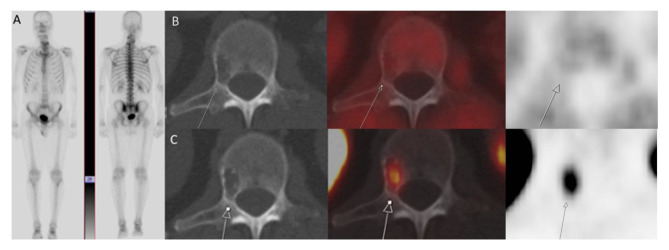

Background: False-positive findings in Prostate-Specific Membrane Antigen Positron Emission Tomography-Computed Tomography (PSMA PET-CT) can complicate accurate staging of prostate cancer, especially in cases such as vertebral hemangiomas, a benign lesion of the spinal column. These ambiguities may result in unnecessary biopsies in patients with prostate cancer when PSMA PET findings are inconclusive.

Case presentation: We present the case of a 68-year-old male with prostate cancer who had a PSMA-expressing, fluciclovine-negative vertebral hemangioma.

Conclusion: This case highlights the role of fluciclovine PET-CT in distinguishing benign vertebral hemangiomas from prostate cancer metastases, improving diagnostic accuracy specifically in positive cases of PSMA PET-CT.